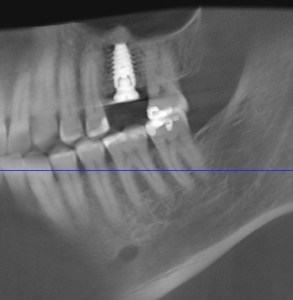

It amazes us how well people can heal sometimes. This case, done by Dr. Wes Parker, involved a 45 year old male who was referred for a carious, necrotic (dead) tooth #14 (upper left first molar). The patient also reported left sided sinus pressure and drainage. At his consultation, we obtained a Cone Beam CT (CBCT) scan. On his CBCT, you could see where the infection and inflammation from tooth #14 had eroded through the floor of the left maxillary sinus. We discussed this with him and scheduled surgery shortly after the consultation. Dr. Parker removed tooth #14, cleaned out the pus and inflamed maxillary sinus lining through the socket. The inflamed, thickened sinus lining went almost up to the orbit (eye socket). Dr. Parker then closed off the sinus communication. Following this, Dr. Parker placed a bone graft over the sinus closure, and then sutured over that to close the wound. The patient healed very well. He was compliant with the sinus precautions and medications that were prescribed. Next, Dr. Parker proceeded with implant placement in the #14 site with a simultaneous indirect sinus lift or “sinus bump.” The implant placement surgery went well, and after about 5 months of healing time, the patient received a crown on the implant from his dentist. Image #1 is a preoperative PA radiograph of the carious, necrotic, nonrestorable tooth #14 (upper left first molar). Image #2 is a coronal slice from the patient’s preoperative CBCT showing the necrotic tooth #14 with a periapical radiolucency and maxillary sinus inflammation stemming from the necrotic tooth. Image #3 is a sagittal slice from the patient’s preoperative CBCT showing the necrotic tooth #14 with a periapical radiolucency and maxillary sinus inflammation stemming from the necrotic tooth. Image #4 is a sagittal CBCT slice from the patient’s post extraction CBCT showing resolution of the sinus inflammation and measurements for the future dental implant. Image #5 is an immediate postoperative PA of the implant in the #14 site following implant placement with a simultaneous indirect sinus lift. Image #6 is a 5 month postoperative PA showing the healed, integrated implant prior to crown placement with a healed sinus lift bone graft above it and no sinus inflammation.